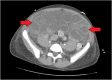

Female with peritonitis and abdominal distention